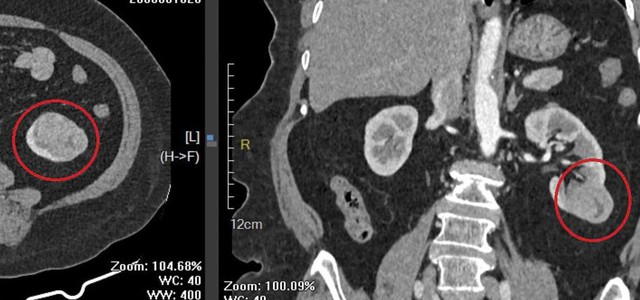

Hình ảnh khối u thận trái của người bệnh qua phim chụp cắt lớp vi tính. Ảnh: BVCC.

Trong quá trình thăm khám và thực hiện các xét nghiệm cận lâm sàng phục vụ phẫu thuật, các bác sĩ phát hiện khối u tại thận trái.

Sau khi hội chẩn và đánh giá toàn diện tình trạng sức khỏe, ê kíp điều trị thống nhất chỉ định phẫu thuật nội soi cắt một phần thận trái chứa khối u, đồng thời bảo tồn tối đa phần nhu mô thận lành nhằm duy trì chức năng thận cho người bệnh cao tuổi.